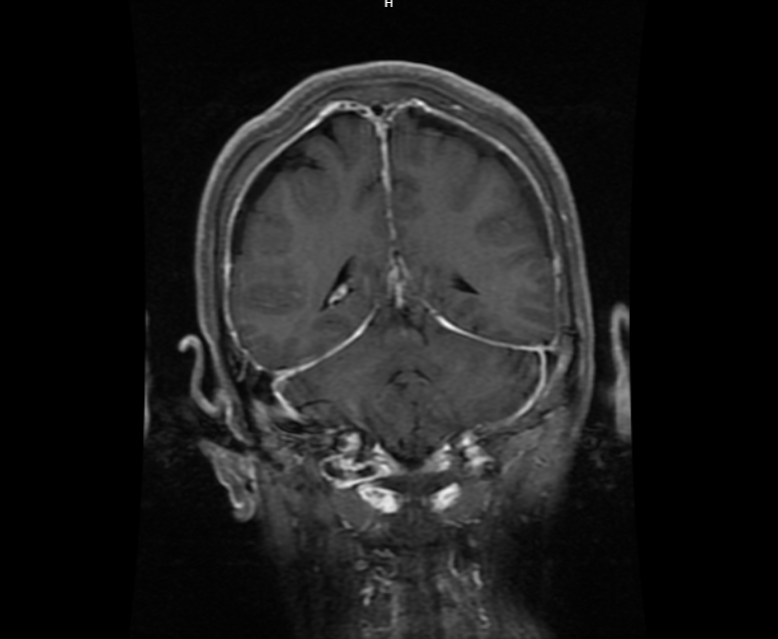

颅脑MRI显示广泛硬膜强化,提示自发性脑脊液漏合并低颅压